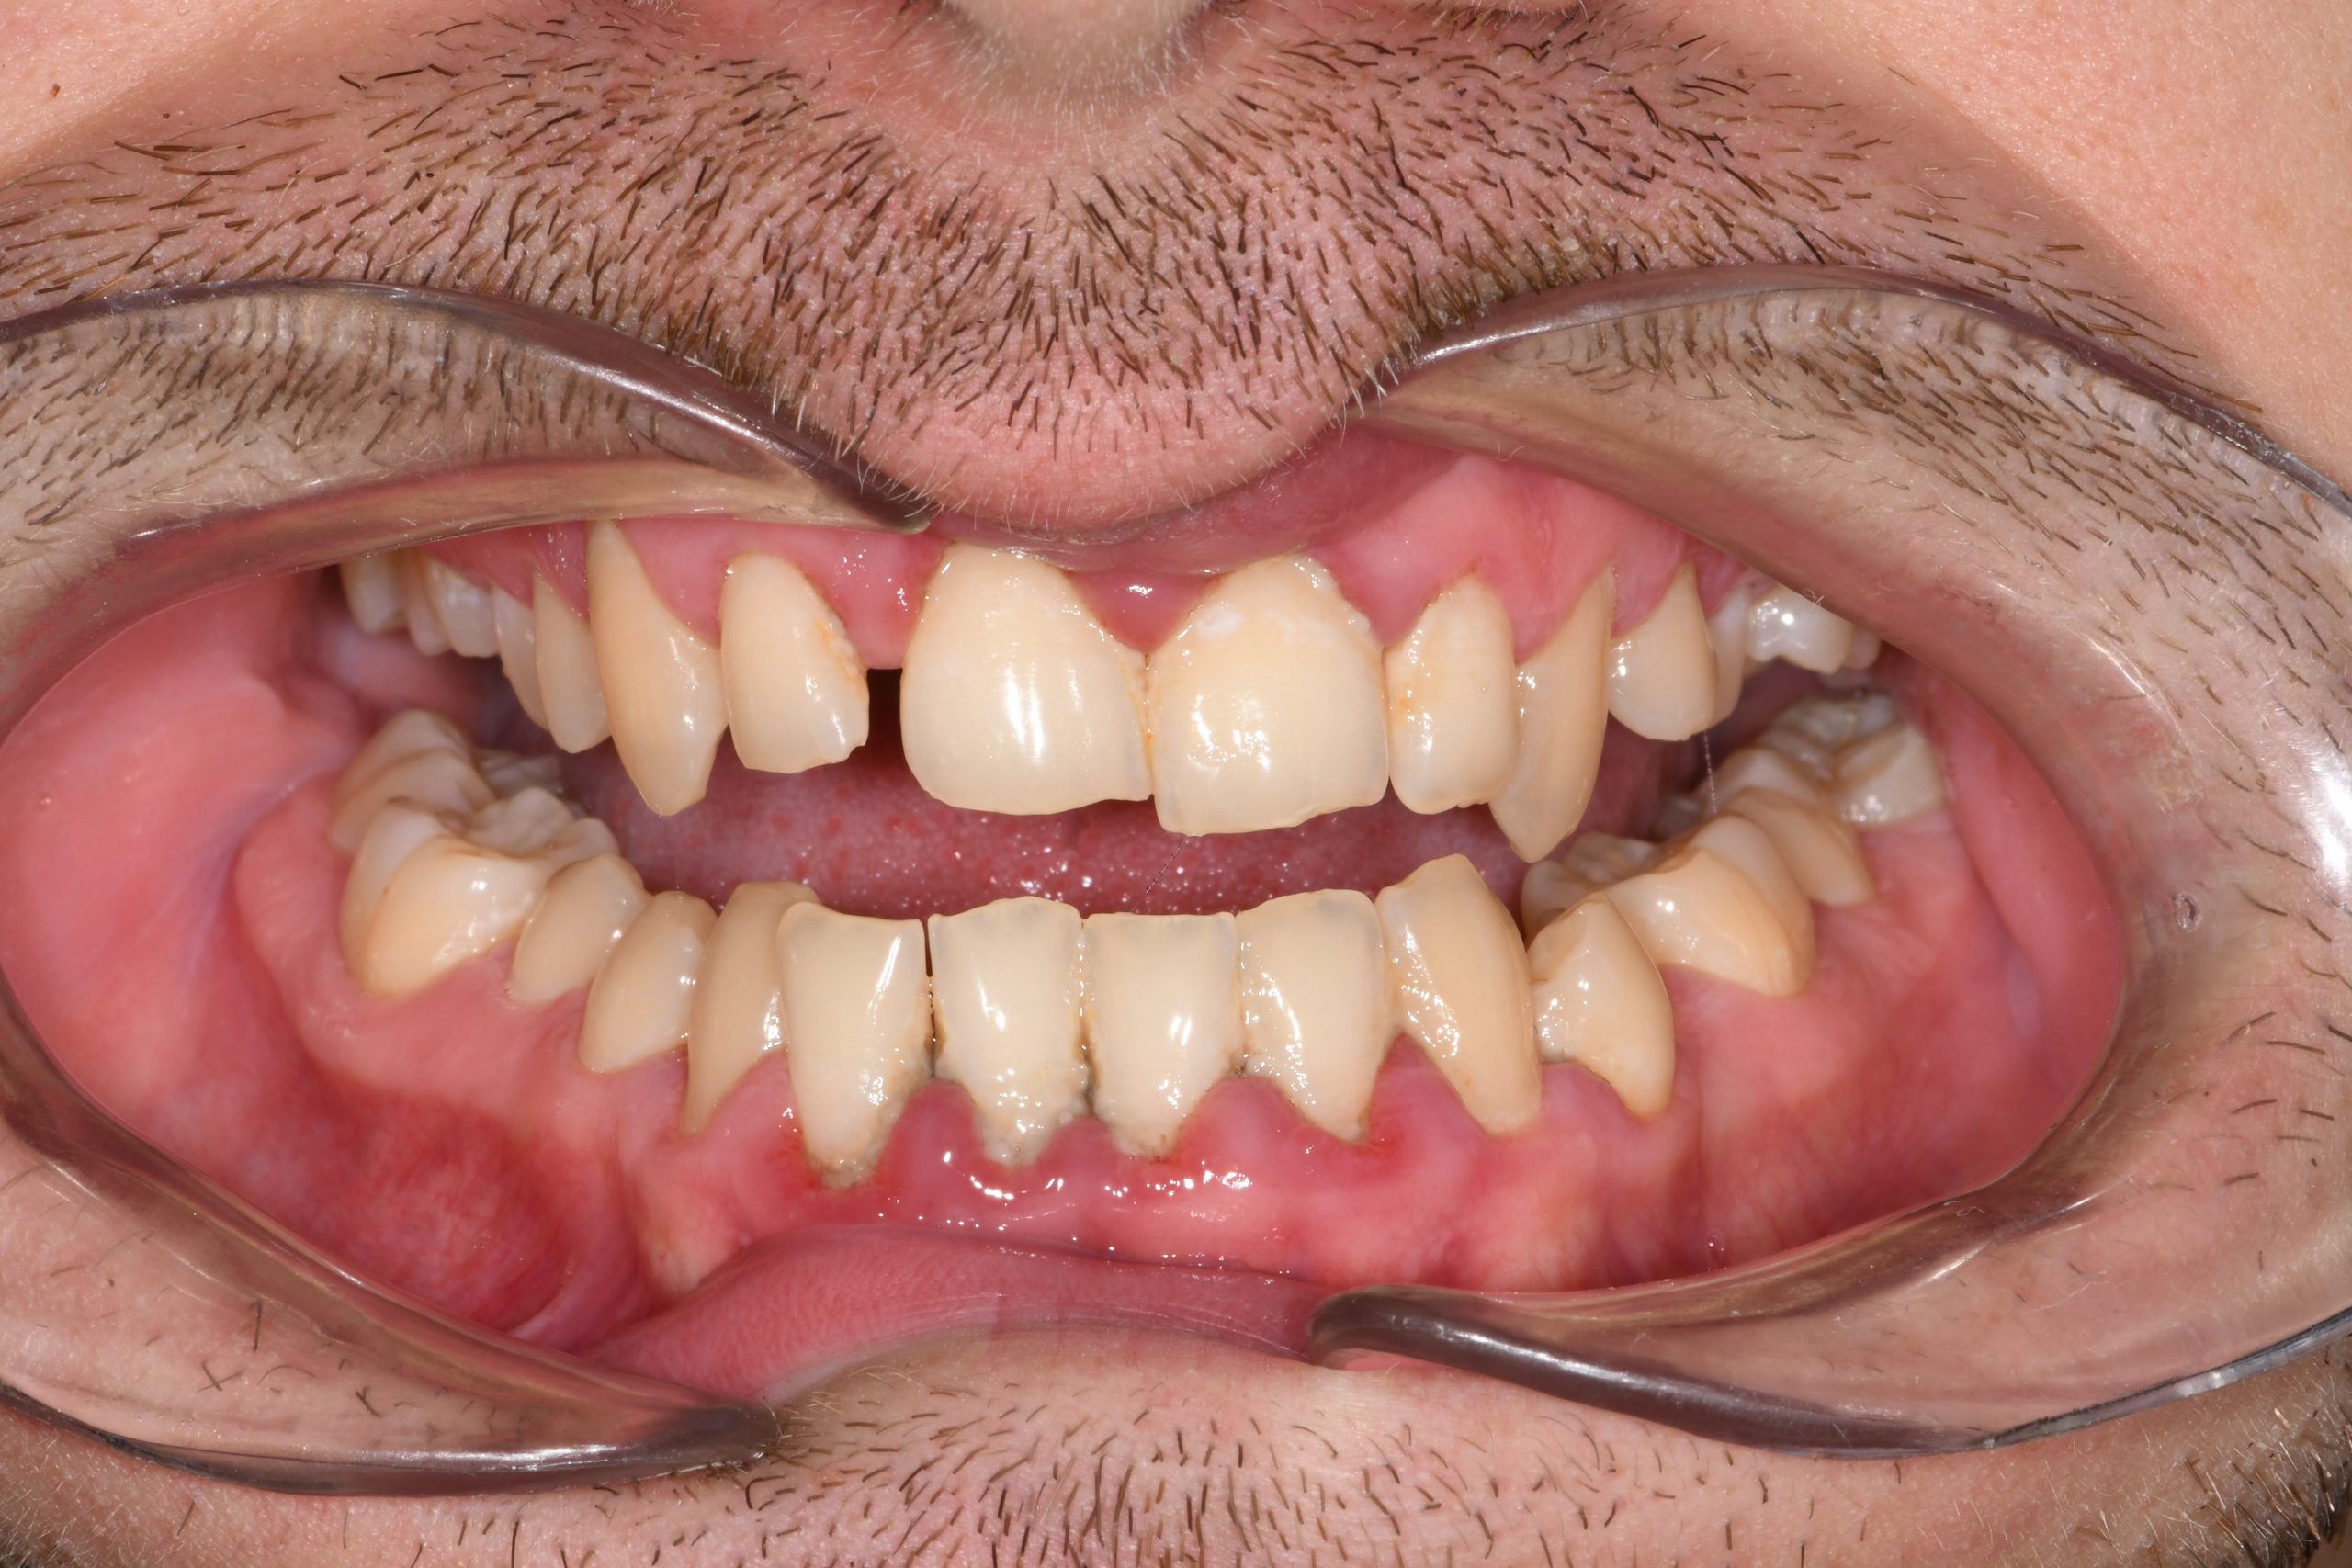

Az elmúlt évekből rengeteg szakmai referenciát tudnánk bemutatni, amelyek különböző fogszabályozási problémákat oldottak meg. Válogatva a több száz esetből, ezen az oldalon olyan képeket, információkat igyekeztünk bemutatni, amelyeknek a segítségével a jövőbeni pácienseinknek azt tudjuk üzenni: A Te fogsorod is lehet gyönyörű!